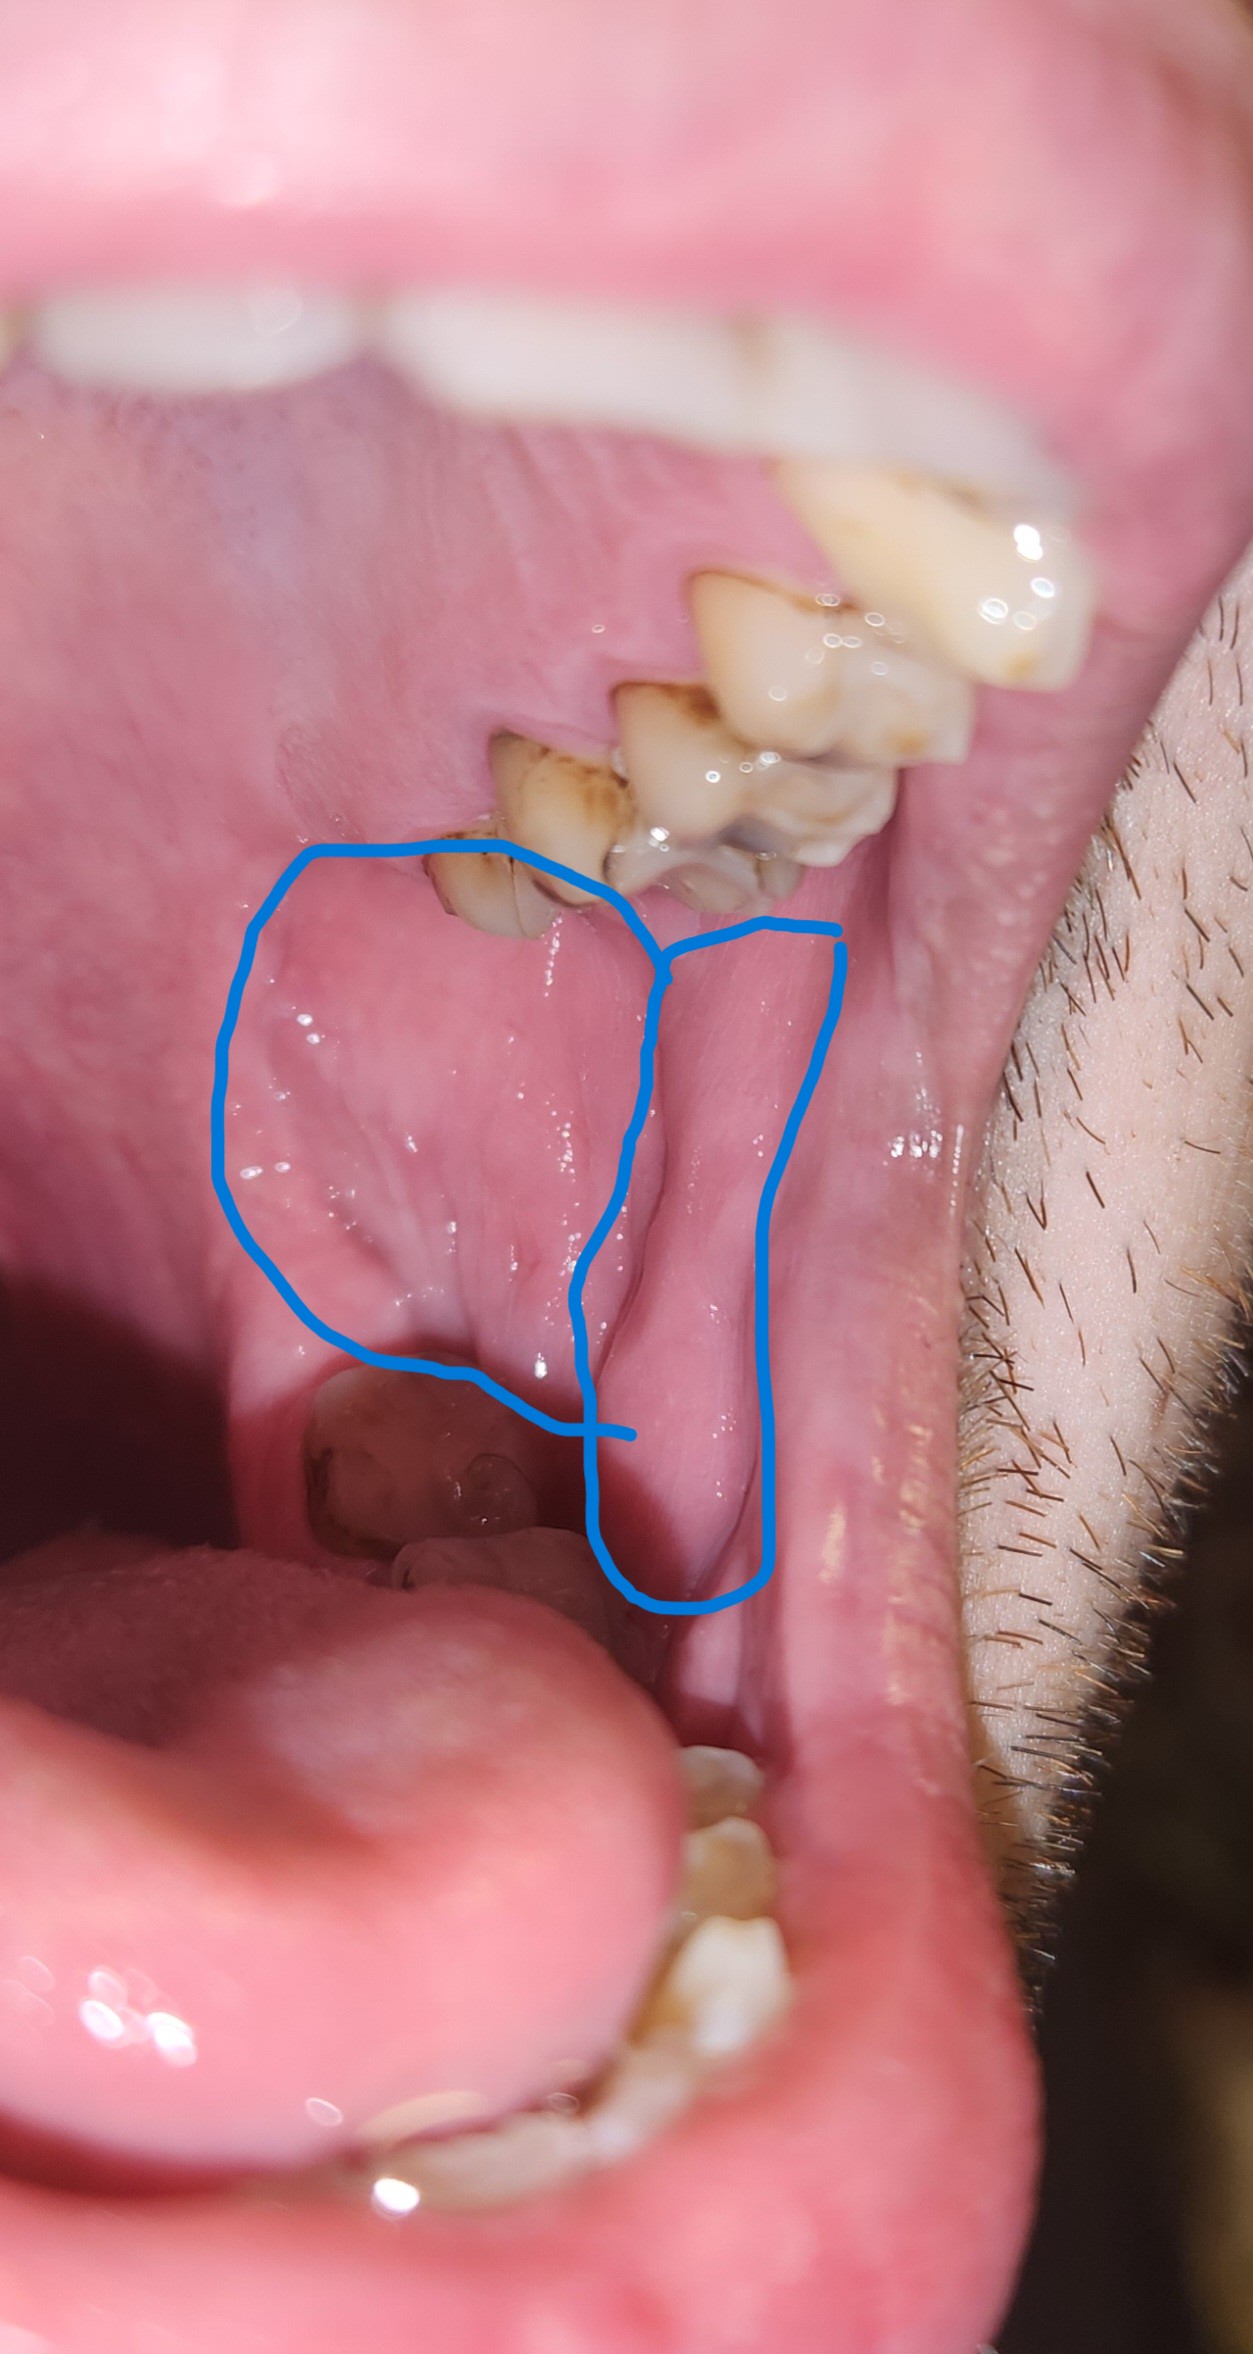

Ich habe seit ca. 3 Wochen eine Schwellung im Mund ohne Schmerzen was könnte das sein ?

ich sehe keine schwellung, nur leichte abdrücke deiner zähne in der wange, was ein zeichen ist, dass du in der nacht presst und knirscht.